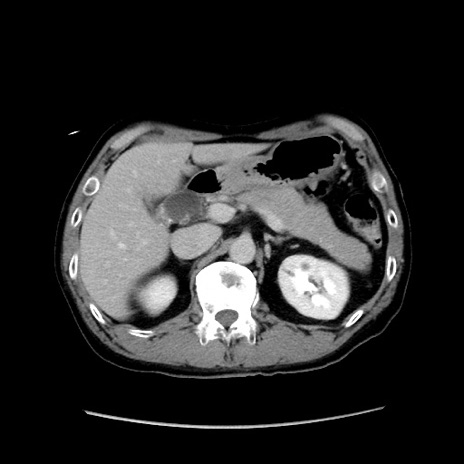

冠状断像